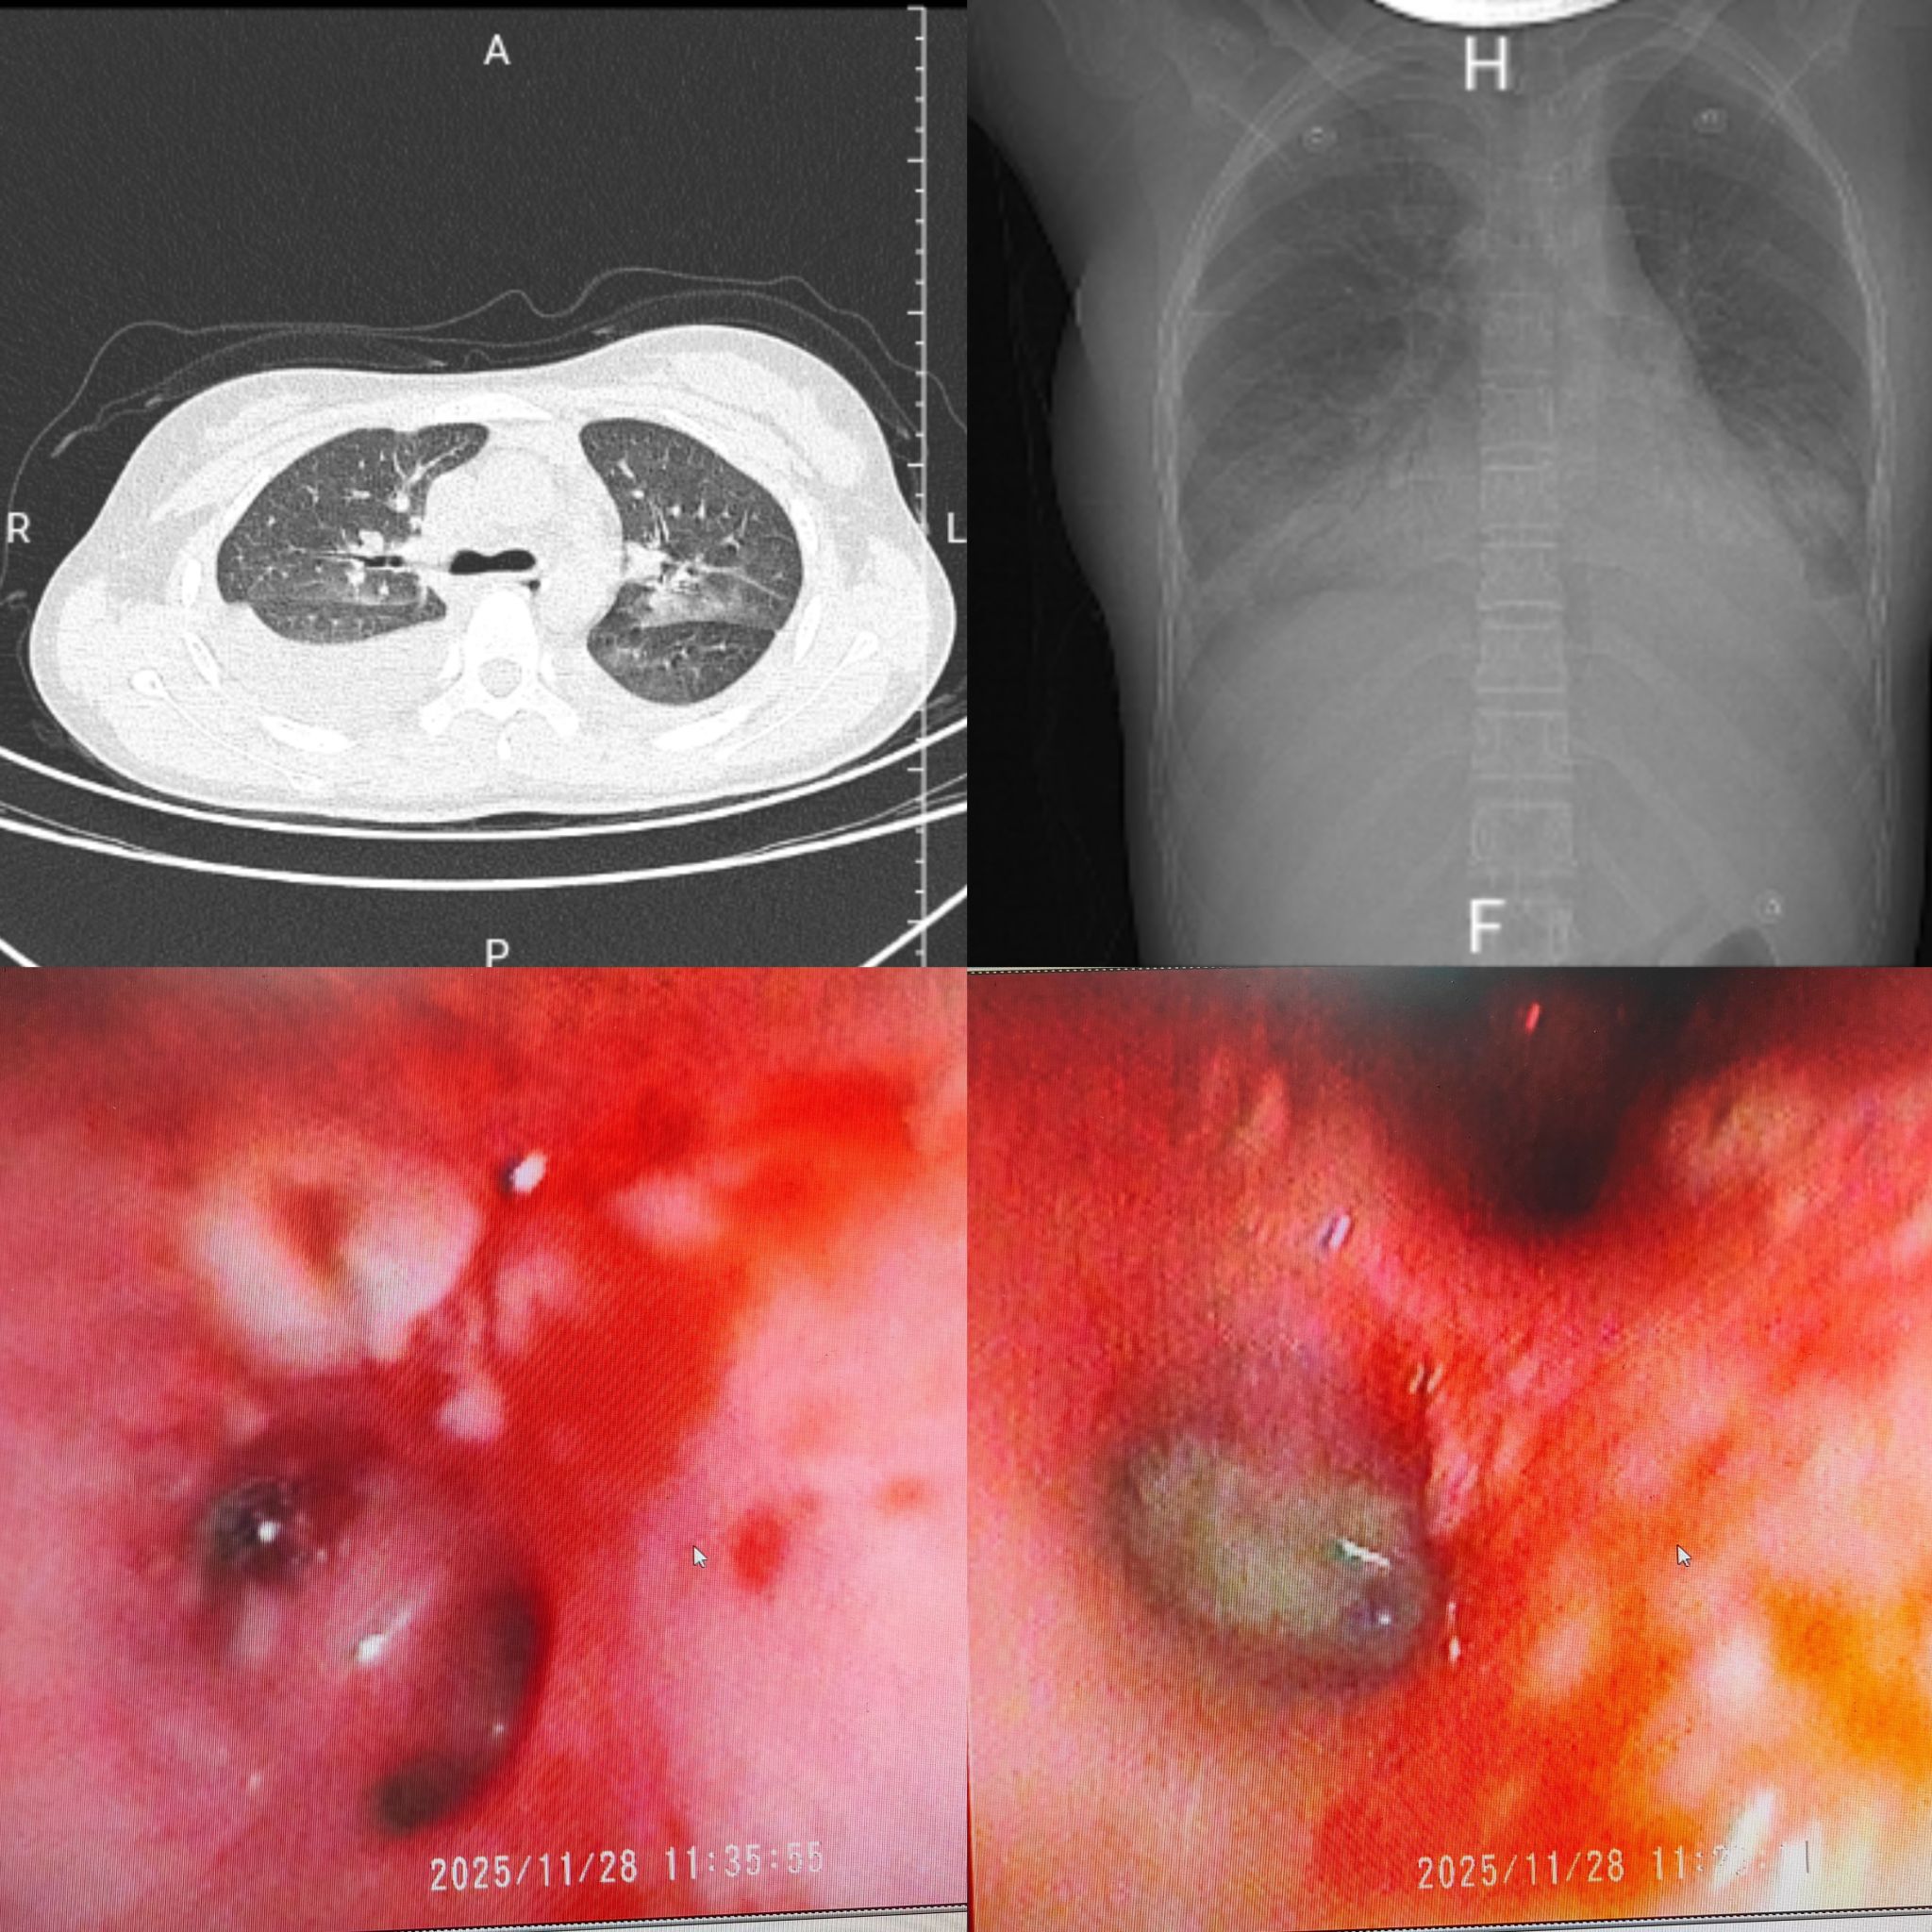

治疗前胸部CT及支气管镜下表现

治疗后胸部CT及支气管镜下表现

该患者因严重呼吸困难、间断发热1周不退于午夜由急诊科紧急转入,入院时患儿已出现明显缺氧表现,鼻导管3L/min吸氧下,仍表现出乏力、胸痛、端坐呼吸等重度呼吸窘迫症状,生命体征极不稳定。PICU迅速集结多学科团队,启动重症救治绿色通道,为患儿争取黄金救治时间。医疗团队快速完成胸部CT、病原学及凝血功能等关键检查,精准判定其为流感病毒感染引发的重症肺炎脓毒症,且合并多脏损伤,随时可能因呼吸衰竭、凝血功能崩溃危及生命而进展为多器官功能衰竭。针对患儿病情,PICU团队迅速制定中西医综合救治方案,给予呼吸支持,启动抗感染及免疫调节集束化治疗,通过床旁纤支镜清除气道分泌物,改善肺通气功能,用宣白承气汤合葶苈大枣泻肺汤、清瘟败毒饮等方剂,以清泻泄热、化痰平喘、通腑逐瘀。

经过24小时紧急救治,患儿呼吸困难症状逐渐减轻,氧合、凝血指标趋于稳定。36小时体温下降,48小时体温、凝血指标恢复正常,胸片显示胸水及实变明显吸收。120小时复查胸部CT,肺部实变、胸水基本消失。168小时各项指标均达正常水平,后续经中医巩固治疗,顺利出院。出院后,医院将对患儿实行危重症全周期随访管理,持续筑牢生命安全防线。